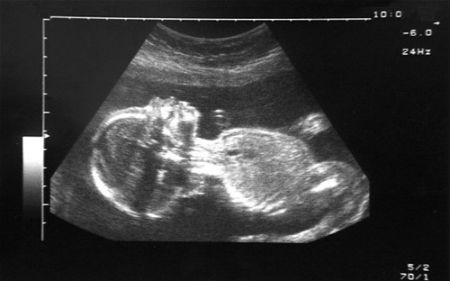

(Kiến Thức) -  Những em bé kỳ diệu này ra đời khỏe mạnh ngay cả khi người mẹ đã chết não, chết lâm sàng nhiều tháng trời.

Em bé chào đời từ người mẹ đã chết não gần 2 tháng. Karla Perez đang mang thai đứa con thứ hai, bị đột quỵ tại nhà ở Waterloo (Nebraska, Mỹ) do xuất huyết não vào ngày 8/3. Cô đã bị chết não. Lúc này, em bé trong bụng Karla được 22 tuần tuổi.

"Em bé trong bụng Karla vẫn ổn nhưng tuổi thai còn quá nhỏ để cân nhắc chuyện đón bé chào đời. Vì thế chúng tôi đã đưa ra quyết định duy trì sự sống cho mẹ để đợi thai cứng cáp hơn", bác sĩ Andrew Robertson, chuyên gia sản khoa tại Trung tâm sơ sinh, Bệnh viện phụ sản Methodist cho biết. Người mẹ trẻ được duy trì sự sống trong 54 ngày, cho tới khi con trai cô, bé Angel, đã sẵn sàng để rời bụng mẹ. Bé được mổ đẻ vào ngày 4/4 và nặng gần 1,3 kg.

Chào đời sau khi mẹ chết lâm sàng 3 tháng. Một em bé Hungary chào đời khỏe mạnh bằng phương pháp mổ đẻ dù người mẹ đã chết lâm sàng 3 tháng trước đó. Các bác sĩ ở bệnh viện của trường Đại học Debrecen, miền đông Hungary, cho biết người mẹ đã bị chảy máu não và chết lâm sàng khi mang thai ở tuần thứ 15 hồi tháng 4/2013. Tuy nhiên, các bác sĩ đã duy trì sự sống cho cô và đứa bé chào đời bằng phương pháp mổ đẻ ở tuần thứ 27 hồi tháng 7. Khi đó, bé nặng 1,4 kg.

“Em bé vẫn khỏe mạnh và phát triển bình thường”, tiến sĩ Bela Fulesdi của bệnh viện cho biết. Tuy nhiên, phía bệnh viện không tiết lộ về giới tính cũng như ngày sinh chính xác của bé. Đại học Debrecen xác nhận hai ngày sau khi sinh, một số bộ phận của cơ thể người mẹ như tim, gan, thận và tụy được chuyển cho 4 bệnh nhân đang chờ người hiến.

Kỳ diệu em bé chào đời từ người mẹ đã chết. Bà mẹ 36 tuổi được chuyển tới cấp cứu tại Bệnh viện San Raffaele, Milan (Italia) vào tháng 10/2014 sau cơn xuất huyết não. Khi đó, đứa bé trong bụng cô mới chỉ được 23 tuần tuổi. Mặc dù không thể cứu được người mẹ, theo yêu cầu của gia đình, các bác sỹ đã quyết định giữ cho cô sống thực vật cho tới khi có thể thực hiện phẫu thuật cứu em bé trong bụng.

Khi thai nhi được 8 tháng, ca phẫu thuật mổ bắt con đã được thực hiện thành công. Bé trai chào đời khỏe mạnh và nặng 4kg. Gia đình bé có nguyện vọng hiến tặng nội tạng của người mẹ để cứu sống những bệnh nhân khác.

Trường hợp tương tự xảy ra tại Mỹ năm 1993 khi cô Trisha Marshall bị bắn chết khi mới mang thai ở tuần thứ 17. Các bác sỹ đã giữ bào thai sống sót suốt 3 tháng trong tử cung người mẹ và cuối cùng em bé cũng được chào đời khỏe mạnh.